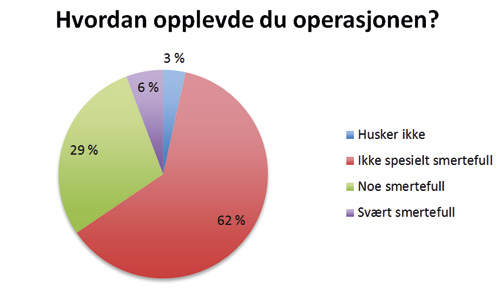

Hvordan opplevde du operasjonen?

Figur 2. Hvordan opplevde du operasjonen?

Den subjektive opplevelsen til pasientene etter behandling av palatinalt retinerte hjørnetenner ved lukket fremføring ble vurdert ut fra svarene fra spørreskjemaet som ble sendt til den enkelte pasient. Vi har ikke funnet noen tidligere studier hvor spørreskjema er benyttet i evaluering av denne type behandling. 90 % av pasientene var fornøyde med resultatet etter behandling. Vår studie viser også at pasientene stort sett er fornøyd uavhengig om pasienten har opplevd smerte under eller etter operasjonen. 20 % av pasientene som oppga at det var svært smertefullt under operasjonen oppga at de ikke var fornøyd med resultatet mot kun 4 % av dem som oppga noe smerter under operasjon. Blant de pasientene som synes at hele prosessen med å få dratt frem hjørnetann var veldig ubehagelig, er det overvekt av pasienter som er fornøyd med resultatet. At 39 av 47 pasientene var fornøyde selv om de svarte at de synes det tok lang tid, gjør at man kan anta at lang behandlingsperiode heller ikke er avgjørende for om pasienten blir fornøyd.

I forbindelse med vevsskade, som ved et kirurgisk inngrep som dette, vil pasientene kunne oppleve sensorisk og emosjonelt ubehag. At 6 % av pasientene opplevde at det var svært smertefullt under en slik operasjon, kan tyde på at det vil være behov for mer fokus på smertekontroll under operasjonene. 21 % av pasientene synes det var svært smertefullt etter operasjonen. Vi ser det er mulighet for at de forespurte pasientene ikke bare har svart om de opplevde postoperative smerter i forbindelse med selve inngrepet, men også om de opplevde smerter i forbindelse med kjeveortopedisk drag av tannen. Ettersom den kjeveortopediske delen av behandlingen også er forbundet med smerte, ser vi at det er behovet for mer nyanserte spørsmål for å få klarhet i dette. Det er også viktig å understreke at dette er en retrospektiv studie, og at det for mange av pasientene er opp til 6 år siden behandling ble utført.